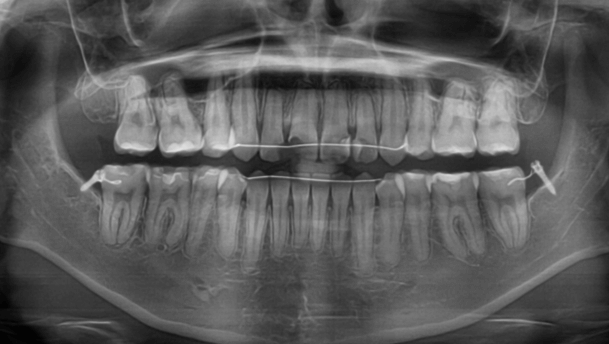

| 年齢・性別 | 15歳の女性 |

|---|---|

| 主訴 | 咬み合わせが逆であること(反対咬合)を気にされて来院された15歳7か月の女性。見た目や機能面の改善を希望されていました。 |

| 治療期間・回数 | 4年4ヶ月・28回 |

| 費用 | 900,000円 |